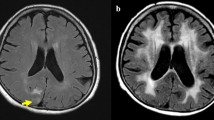

Glioma is the second most common radiation-induced intracranial tumor after meningioma. In one analysis of patients treated with sellar radiation for pituitary adenomas, the relative risk of glioma was 7.9 times higher than that of the normal population [11]. The vast majority of radiation-induced gliomas are WHO grade III astrocytoma (anaplastic astrocytoma) or grade IV astrocytoma (glioblastoma; Fig. 2) [12]. In a review of 176 cases of radiation-induced glioma, Elsamadicy and colleagues reported a 9-year median latency period, with over 80% of cases occurring within 15 years of radiation [13]. As with meningioma, most radiation-induced gliomas occurred in young adults who were children at the time of initial radiation (Fig. 2).

Radiation-induced glioblastoma. A 30-year-old man with a right cerebellar hemisphere glioblastoma approximately 20 years after treatment of cerebellar medulloblastoma. Axial post-contrast T1-weighted image (a) and FLAIR image (b) demonstrate a ring-enhancing mass with surrounding T2 hyperintensity.

Imaging findings of radiation-induced gliomas are similar to those of sporadic tumors and depend on the specific tumor type. Thus, while it is important to suggest the diagnosis based on the appearance of a new, aggressive-appearing tumor, biopsy is often ultimately necessary. Median overall survival in this review was less than 1 year, which is worse than malignant glioma overall, especially considering the relatively young age of the radiation-induced malignancy patient population [14].